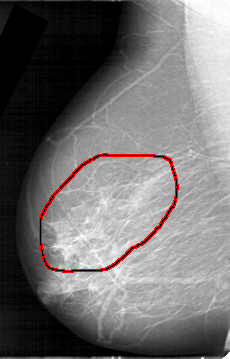

FILE: D_4149_1.RIGHT_CC.OVERLAY

TOTAL_ABNORMALITIES 1

ABNORMALITY 1

LESION_TYPE CALCIFICATION TYPE AMORPHOUS DISTRIBUTION SEGMENTAL

ASSESSMENT 0

SUBTLETY 3

PATHOLOGY MALIGNANT

TOTAL_OUTLINES 1

BOUNDARY